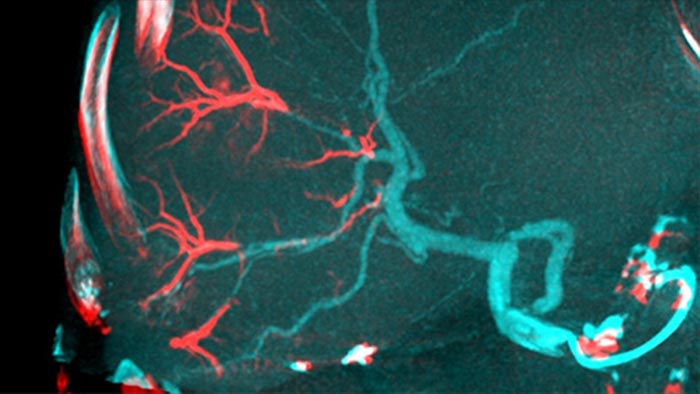

Ao abrir o arco à esquerda do paciente, a CBCT aberta permite o posicionamento descentrado da mesa do paciente e, portanto, uma melhor centragem do FOV3-4. Isto aumenta significativamente a cobertura da imagem para ajudar a visualizar tumores na periferia do fígado.4